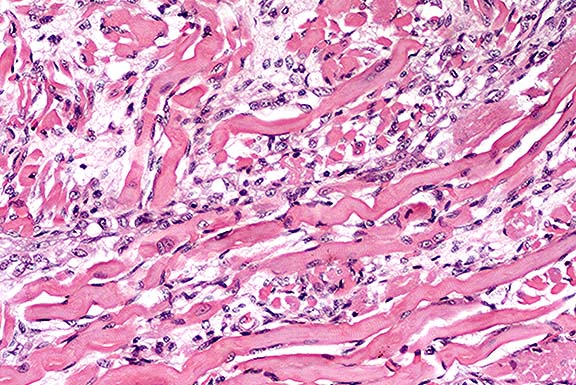

Contributor's Diagnosis and Comments: Skeletal muscle, tongue: Severe, diffuse, polyphasic muscle necrosis and regeneration, Golden Retriever cross, canine.

Tongue: There were few areas of normal striated muscle within the tongue. Variation in fiber size associated with muscle degeneration and regeneration was a prominent feature. Degenerate muscle fibers appeared swollen with increased eosinophilia, whereas regenerating muscle fibers were narrow with variable cross sectional diameter and occasional central nuclei. Evidence of muscle regeneration was also demonstrated by prominent clusters of plump myonuclei lining up along the edge of myofibers.

Segmental necrosis of muscle fibers was often accompanied by increased basophilia due to mineralization. Areas of increased tissue basophilia were associated with infiltrates of macrophages and skeletal muscle precursor cells associated with myofiber regeneration.

GRMD is a genotypic and phenotypic homologue of Duchenne muscular dystrophy (DMD) (B.J Cooper et al 1988). In both humans and dogs with dystrophin deficiency there is phenotypic variation in the clinical progression of the disease between individuals. One manifestation of dystrophin deficiency recorded in dogs is a lethal neonatal form (J.McC Howell et al 1994; B.A Valentine et al 1988). Pups presenting with this form of the disease usually have serum creatine kinase levels greater than 1000 times the normal adult range at birth, and die before 14 days of age (B.A Valentine et al 1988; J.McC Howell et al 1994). At post mortem there is severe muscle necrosis and mineralization consistently involving the diaphragm and intercostal muscles (J.McC Howell et al 1994). Muscles severely affected by necrosis and mineralization in this pup included the tongue, trapezius, intercostal and sternocephalicus muscles. Cardiac lesions are usually absent until after 3 months of age (B.A Valentine et al 1989).

The presence of a range of degenerative and regenerative stages within the skeletal muscle of the tongue at 3 days of age indicates muscle necrosis associated with GRMD can occur in utero. These features are consistent with the progression of clinical disease documented by Valentine et al 1988.

Case 11-3. Tongue. Note clusters of small round regenerating muscle fibers. Degenerate (hyalinized) muscle fibers are occasionally lined by myocyte nuclei (nuclear rowing) and separated by endomysial fibroplasia.

AFIP Diagnoses:

1. Tongue, skeletal muscle: Degeneration and necrosis, diffuse, severe, with endomysial fibrosis, myocyte regeneration, and mild lymphohistiocytic inflammation, Golden Retriever cross, canine.